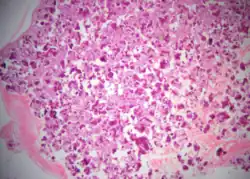

Histopathology

Cemento-ossifying fibroma is a well-demarcated lesion, often encapsulated by a thin fibrous capsule and sharply separated from adjacent normal bone. It shows significant internal variation, with differing amounts of fibrous and mineralized tissue—even within the same lesion. Mineralization is often more prominent centrally and typically includes osteoid, woven to lamellar bone, and dense basophilic cementum-like calcifications. Bony trabeculae may fuse into broad sheets or form thick, anastomosing strands. Osteoblastic rimming is commonly seen around bone trabeculae.[27]

The stroma is fibroblastic and may exhibit areas of hypercellularity and nuclear hyperchromasia; however, mitotic activity is rare and cellular atypia is minimal .[28] The mineralized component may include acellular or paucicellular cementum-like spheres along with bone structures .[28]

Though rare, hemorrhagic cystic degeneration—resembling aneurysmal bone cyst formation—can occur, more commonly in juvenile variants.[27][29] Histological overlap can exist among subtypes: psammomatoid and trabecular JOF may exhibit features resembling COF, and vice versa. In syndromic cases, such as gnathodiaphyseal dysplasia, COF lesions appear more fibrous with basophilic, acellular bone droplets and spherical ossicles, but histologically resemble nonsyndromic counterparts .[30]